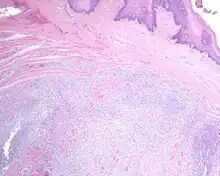

An intermediate power hematoxylin and eosin stained section of an ectomesenchymal chondromyxoid tumor, showing skeletal muscle entrapment. Note the "net-like" appearance (lower portion).[5][6] The overlying surface epithelium is intact and unconnected to the well circumscribed, but unencapsulated ectomesenchymal chondromyxoid tumor of the tongue. There are numerous skeletal muscle bundles at the periphery of the tumor.

The overlying surface epithelium is intact and unconnected to the well circumscribed, but unencapsulated ectomesenchymal chondromyxoid tumor of the tongue. There are numerous skeletal muscle bundles at the periphery of the tumor. - The tumor is made up of small round, oval, spindle, or stellate cells that have a very monotonous appearance. There are small dark nuclei with variably amounts of light to basophilic cytoplasm.[1][5][7]

- There is a background stroma composed of chondromyxoid to myxoid material. Sometimes large cells are seen in chondroid or cartilaginous areas. Swirling formations give the appearance of neural tissue.[7]